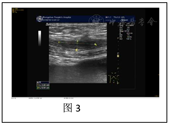

(1)2021年9月20日急诊B超:宫内单胎妊娠;宫内异常回声团块,考虑血块可能,胎盘显示不清,以上征象未排胎盘早剥可能。未及胎心。BPD:93 mm,HC:323 mm,AC:285 mm,FL:66 mm。宫腔内见一高回声为主团块,范围约136 mm×49 mm(图1)。(2)术中床旁经食管心脏超声提示右心室增大,肺动脉高压声像(图2)。

诊断依据:两次剖宫产史,围分娩期出现典型的无法用其他原因解释的突发心脏骤停,凝血功能障碍,术中食管心脏超声见肺动脉高压声像图,典型的腹痛、阴道流血、无间歇的宫缩、板状腹、未闻及胎心,B超见宫内异常回声考虑血块可能,未见胎儿心跳,凝血功能检查提示APTT、凝血酶原时间延长,纤维蛋白原极低,3P阳性,D二聚体异常升高,产后24 h估计总出血量4 100 ml。紧急行剖宫取胎术,住院期间最低血红蛋白78 g/L,入院血压稍高,术后血压超过160/110 mmHg,产后一直需要降压药控制约10 d,伴器官功能损害。

羊水栓塞的诊断主要是依靠具有相关高危因素的患者的典型临床表现进行的,辅助检查主要作用是在抢救过程中监测病情进展和进行回顾性确认。回顾本例患者临床经过,患者符合上述诊断条件,羊水栓塞诊断明确。程宁宁等[5]分析了61例羊水栓塞病例报道,发现仅2例(3.3%)没有高危因素。本例患者存在高龄、经产妇、宫缩过强等多个羊水栓塞高危因素,临床医师需在围分娩期对有羊水栓塞高危因素患者进行提高警惕性严密监测和管理。程宁宁等[5]分析文献报道资料显示羊水栓塞临床表现涵盖多个系统的功能障碍复杂多样,主要有循环功能障碍85.2%,呼吸功能障碍77.0%,血液功能障碍63.9%,神经功能障碍45.9%,肾功能障碍8.2%,肝功能障碍1.6%。本文作者亦复习了国外11例羊水栓塞合并心脏骤停[6,7,8,9,10,11,12,13,14,15]文献资料发现有循环功能障碍11/11,血液功能障碍11/11,呼吸功能障碍6/11,神经功能障碍5/11,肾功能障碍1/11,胎盘功能障碍1/11,3个以上系统功能异常11/11。本例患者病程中出现了胎盘功能障碍、肾功能障碍、循环功能障碍、血液功能障碍,到院时均已存在,各系统累及的先后顺序已很难追溯,本案例和相关的文献资料提醒临床医师,当一个既往孕产史及病史无特殊的孕妇围分娩期出现任何一个突发的功能障碍均应疑诊,出现多个功能障碍时更应警惕暴发性羊水栓塞,尽快启动抢救流程。国外11例羊水栓塞合并心脏骤停[6,7,8,9,10,11,12,13,14,15]。文献资料显示11例患者抢救过程中经食管超声均显示有右心衰表现,和本文病例相符,其中1例在心脏骤停抢救后1 h左右,病情相对平稳时复查经食管超声发现右心功能已经恢复基本正常[13]。提示有条件的医疗机构在羊水栓塞抢救中进行该项检查可以协助诊断和指导治疗。